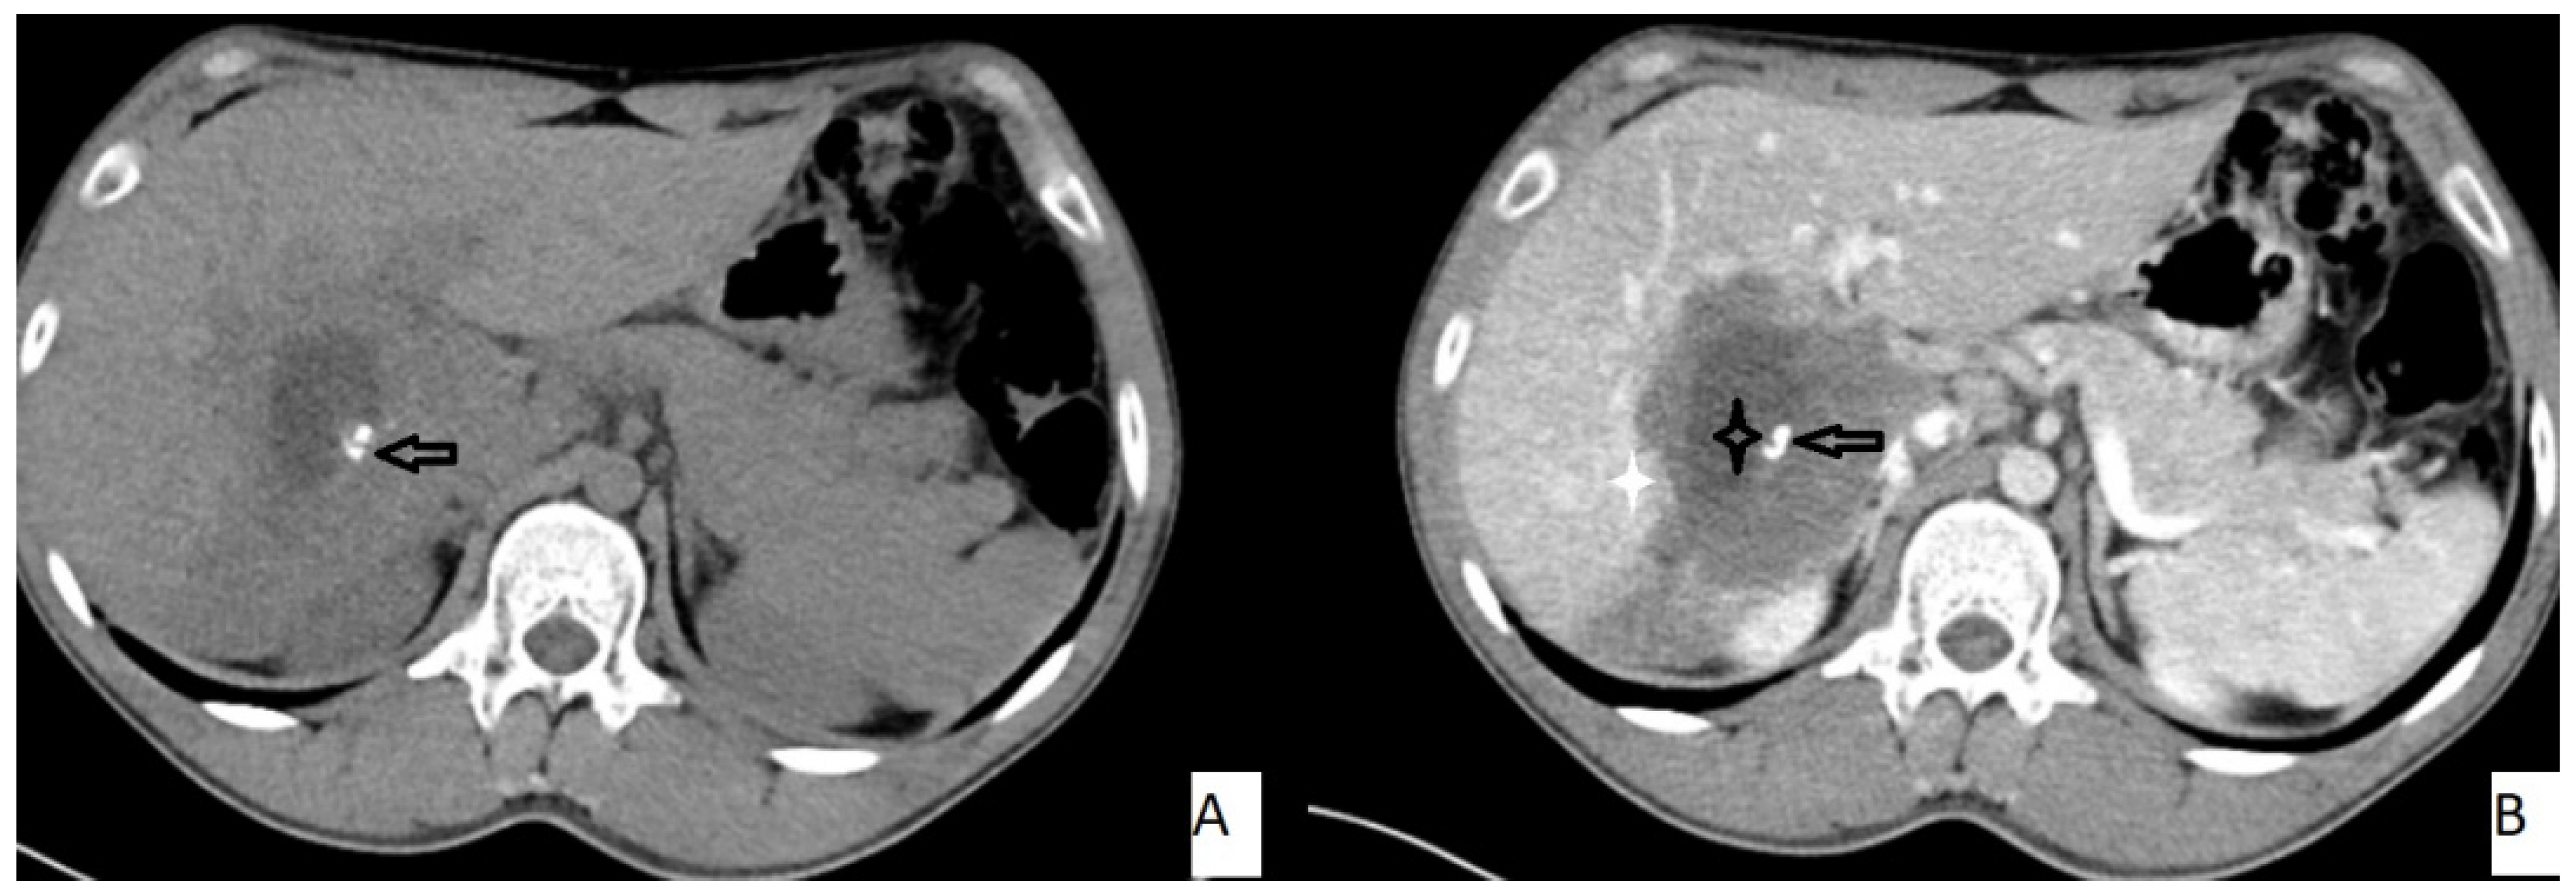

The most frequently encountered CT pattern was a heterogeneous mass with calcifications and hypoattenuating areas (72.3%). Most of the lesions had irregular contours (85.4%), 85.4% lacked contrast enhancement, 77.4% of the lesions had calcifications, and atrophy and capsular retraction was present in 10.7% of the lesions (Figure 2 and Figure 3). Table 3 details the distribution of CT appearances.

Figure 2.

51-year-old male. Hepatic lesion with irregular contours and calcifications on precontrast axial CT (A). On portal venous images (B), no enhancement is present in the lesion. Central necrosis can be seen (A,B—black star). Perilesional enhancement (B—white star) and capsular (A,B—arrows) retraction are present.

Figure 3.

53-year-old female. Hepatic lesion with irregular borders and calcification (A,B—arrows) on precontrast axial CT (A). On portal venous images (B), no enhancement is present in the lesion. Central necrosis can be seen (B—black star). Perilesional enhancement (B—white star) is present.